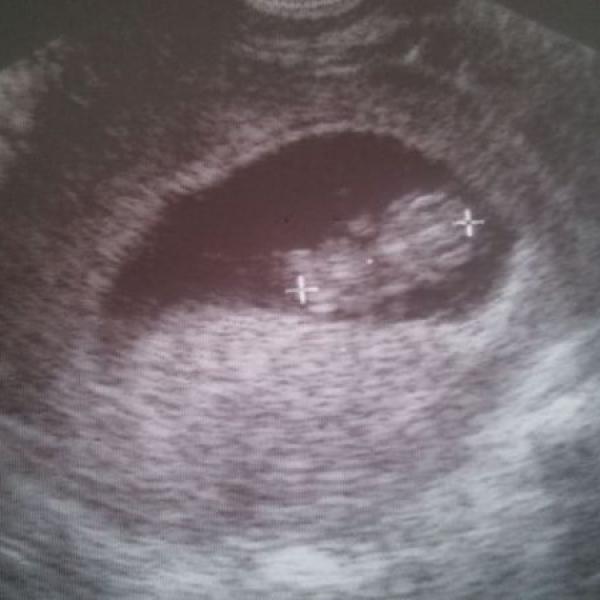

Ahoj holky... Tak jsme vcera byli na tom screeningu v I.trimestru. Nejdriv mi doktor delal UTZ pres brisko a ze tam neni moc videt, tak me poslal vyslect ze udela jeste vaginalni...